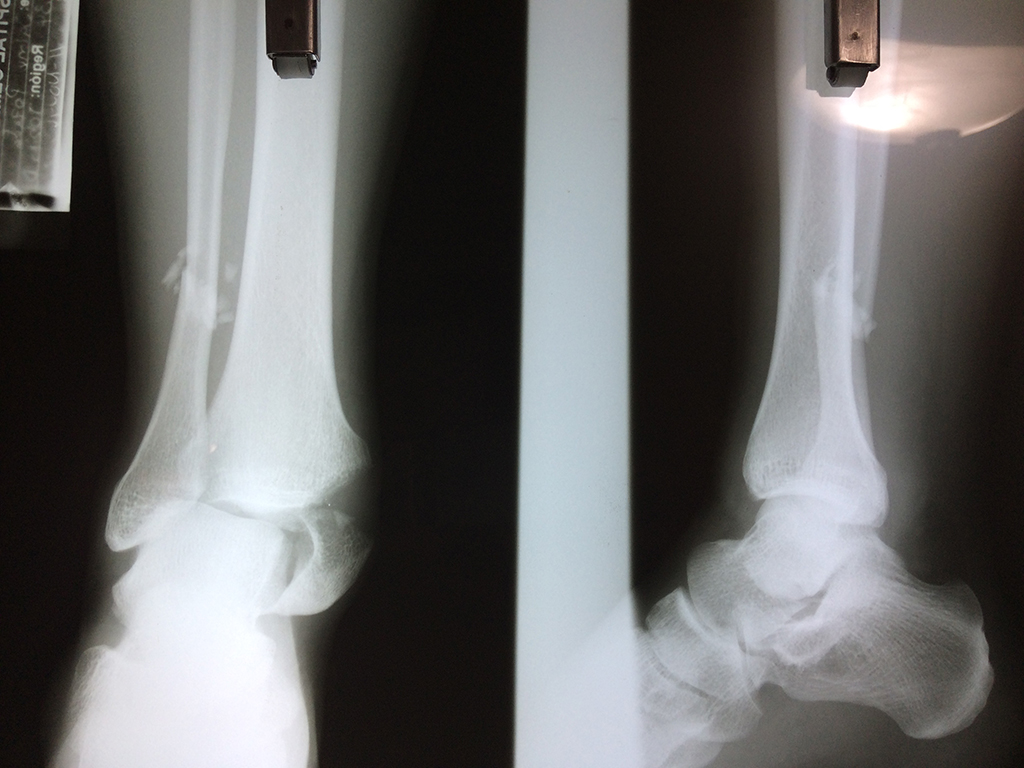

Una fractura de tobillo es la rotura de uno o más de los huesos del tobillo. Estas fracturas pueden ser: